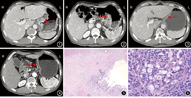

患者男,45岁。因发现贲门部肿瘤1周入院。患者于2017年4月,健康体检发现肿瘤指标CEA为12.05 μg/L,行胃肠镜检查示胃贲门肿瘤,收入我院。入院体格检查:患者营养风险评分为1分,一般情况尚可,生命体征平稳,心肺正常,腹部平软,锁骨上淋巴结未扪及肿大。患者2017年4月18日行辅助检查:(1)胃镜检查示贲门癌(肿瘤距门齿40~50 cm);慢性浅表性胃炎(胃窦为主);幽门螺杆菌阳性。(2)病理学检查示中分化胃贲门腺癌,Lauren分型为肠型;胃窦中度慢性胃炎,中度肠化,中度萎缩,间质充血,有中性粒细胞浸润。患者4月19日行辅助检查:(1)胸腹部增强CT检查示胃贲门部胃黏膜不均匀增厚(图1),最厚处约18 mm,胃周见多发肿大淋巴结影,大小为19 mm×18 mm,增强扫描增厚胃壁可见明显强化,考虑诊断:食管胃结合部恶性肿瘤,胃周淋巴结转移(图2)。(2)上消化道造影检查示钡剂通过食管受阻,稍狭窄,贲门、胃底见充盈缺损,考虑诊断:食管下端、贲门、胃底区癌。患者明确诊断:食管胃结合部腺癌,ctT4aN+M0期。

患者2017年5月19日开始行XELOX方案(21 d为1个周期)新辅助化疗;2017年6月12日行第2次疗程化疗和胃局部调强放疗,DT 45 Gy/25F;2017年6月22日行第2次胃局部调强放疗,DT 45 Gy/25F。患者放化疗期间发生胃肠道、血液系统相关不良反应。2017年8月23日患者复查胸腹多排螺旋CT示食管胃结合部管壁增厚程度较前明显减轻(图3),最厚处9 mm,肝胃韧带多发小淋巴结,较前明显缩小(图4),最大者8 mm。

王秋实主任医师(影像科):实体瘤疗效评价标准(RECIST)是目前国际通用的实体肿瘤评效准则,但其在胃肠道癌新辅助化疗的应用却遭遇瓶颈[7]。胃癌原发灶测量的一致性和可重复性差,不建议作为可测量靶病灶;而肝、肺或淋巴结转移病灶作为靶病灶,具有良好的测量一致性和可重复性,但极大减少了可评效患者的数量。本例患者治疗后,原发病灶受胃腔形态、充盈度影响,无法准确测量病灶长径;病灶厚度略变小;溃疡显示不清晰;贲门胃壁仍增厚并全层强化,强化减低;胃周间隙较放化疗前清晰,评估为T3a期。胃周淋巴结明显缩小,其中胃小弯侧淋巴结短径9 mm,内仍见坏死,评估为N1期。患者经放疗和化学治疗后TNM分期评估为T3aN1M0期。

患者于2017年9月7日,在全身麻醉下行经胸腹联合切口,腹腔镜辅助食管胃结合部癌根治性(R0)切除术,消化道重建方式选用食管胃端侧侧吻合Ivor-Lewis。患者手术顺利,术后予以抗感染、抑酸和肠内外营养等相关对症支持治疗,术后16 d出院。术后病理学检查:胃贲门肿瘤新辅助化疗后,未见癌残留(图5);上下切缘阴性;共送检17枚淋巴结(下纵隔淋巴结2枚、第2组淋巴结2枚、下食管旁淋巴结2枚、胃小弯侧淋巴结11枚),1枚第2组淋巴结发生转移(图6),ypT0N1M0期。患者术后1个月选用XELOX方案行3个疗程化疗。患者术后定期随访,随访时间截至2018年6月患者恢复良好。

武鸿美主治医师(病理科):新辅助治疗后肿瘤消减的组织学标志为泡沫细胞聚集、吞噬含铁血黄素的组织细胞反应、胆固醇结晶析出、异物巨细胞反应、营养不良性钙化。此例患者术后在广泛取材病理学检查显示:原发灶并未见癌细胞残留,间质纤维化及炎细胞浸润(肿瘤自身坏死亦可引起该现象),未见明显泡沫细胞聚集。根据胃癌新辅助治疗肿瘤消减分级两大系统:Mandard TRG 1:完全缓解=纤维化,无可检测的肿瘤组织;Becker TRG 1a:无残留肿瘤或肿瘤床+化疗效果。可判定本例患者为原发病灶的病理学完全缓解[8,9]。送检第2组淋巴结可见腺癌转移。